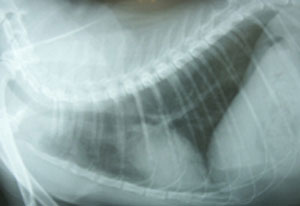

胸部X線検査所見:肺野および心陰影に異常を認めず(図1)。

図1 症例1の初診時胸部X線写真。肺野および心陰影に異常を認めなかった。